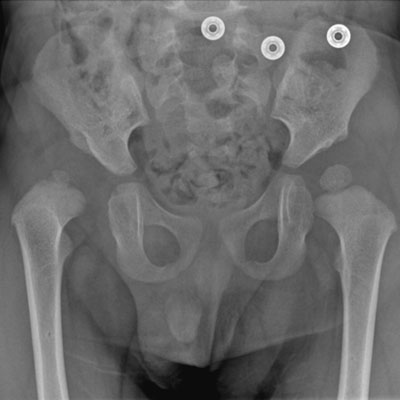

Proximal Femoral Growth Alterations Can Be Seen Prior to Treatment of Developmental Dysplasia of the Hip: A Multicenter Cohort Study

Patrick England, Emily Schaeffer, Charles Price, Kishore Mulpuri, Global Hip Dysplasia Registry (GHDR), Wudbhav N. Sankar